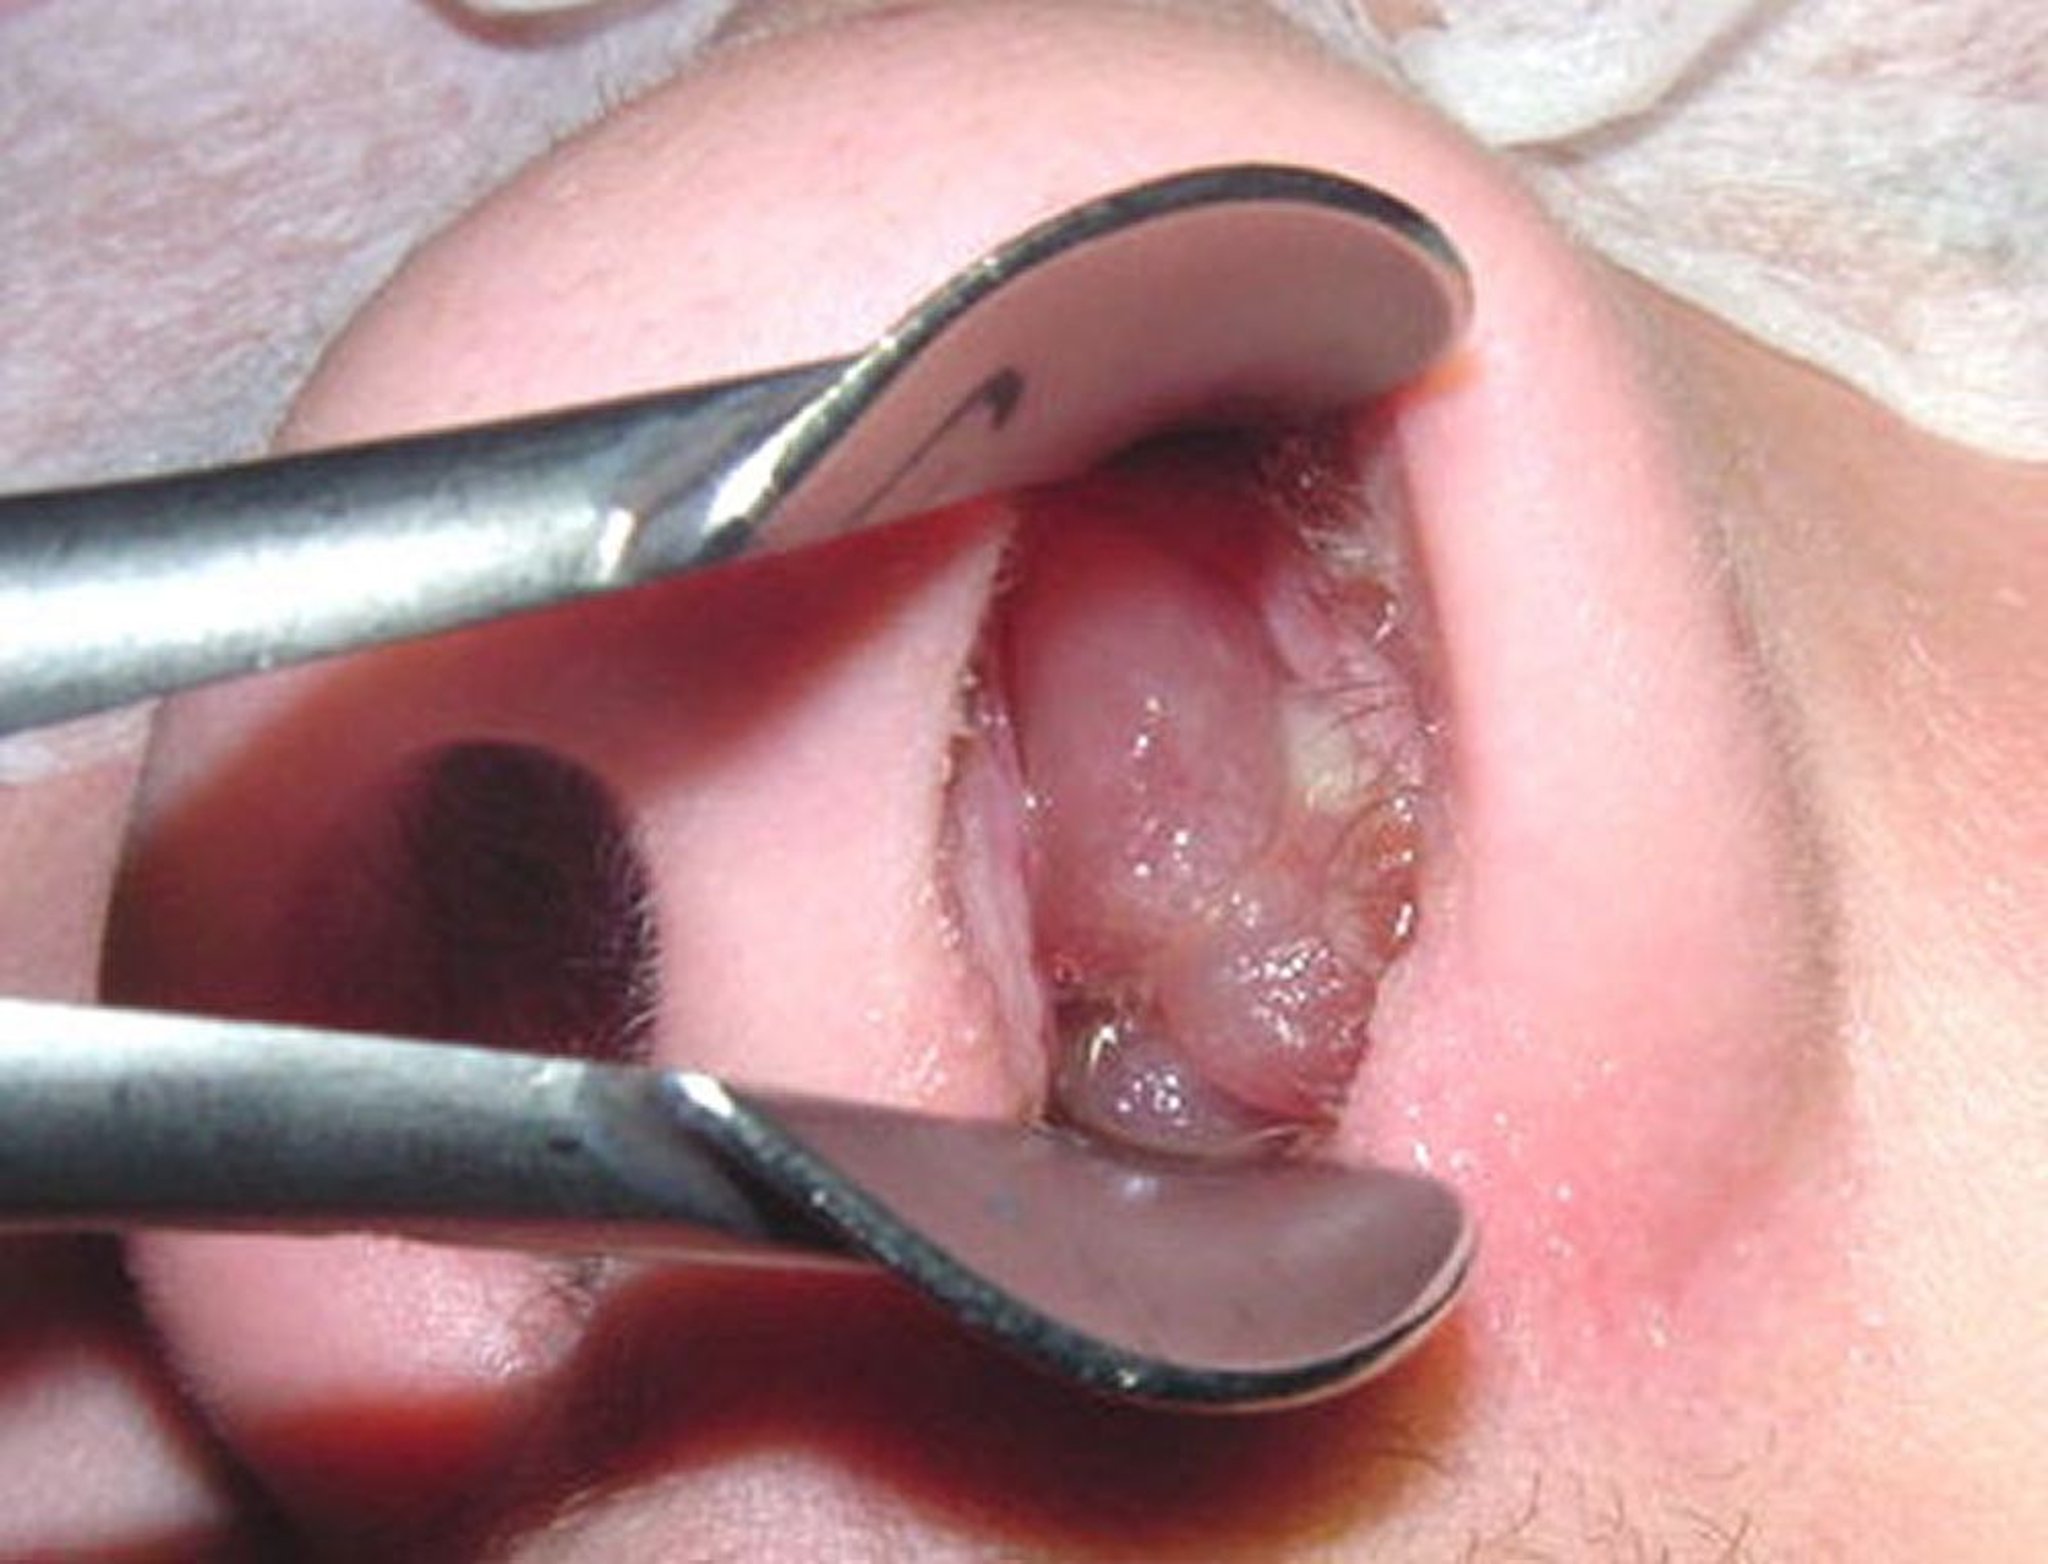

비용종

성숙된 비용종은 껍질이 벗겨진 씨 없는 포도알을 연상시킬 수 있습니다.

이미지 제공: Bechara Ghorayeb, MD.